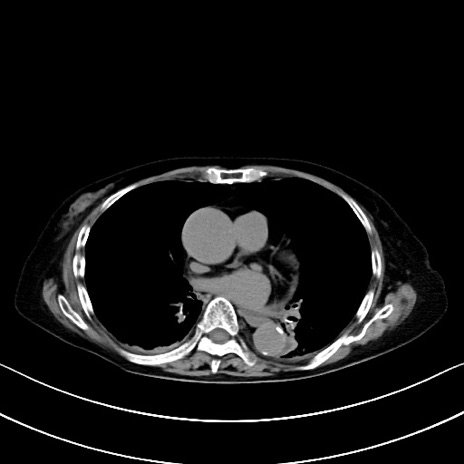

横断像